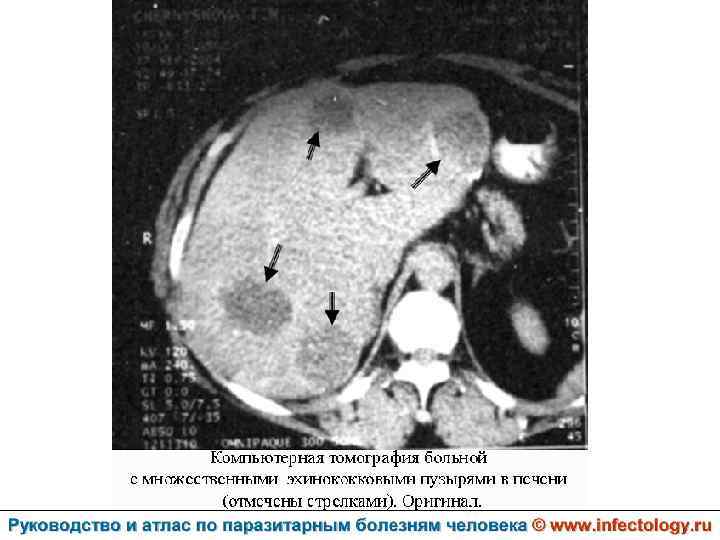

Цистный эхинококкоз (цистный гидатидоз) (шифр по МКБ 10 - B 67. 0 -4) – зоонозный биогельминтоз, характеризующийся хроническим течением, образованием кист и деструктивным поражением печени, легких и других органов.